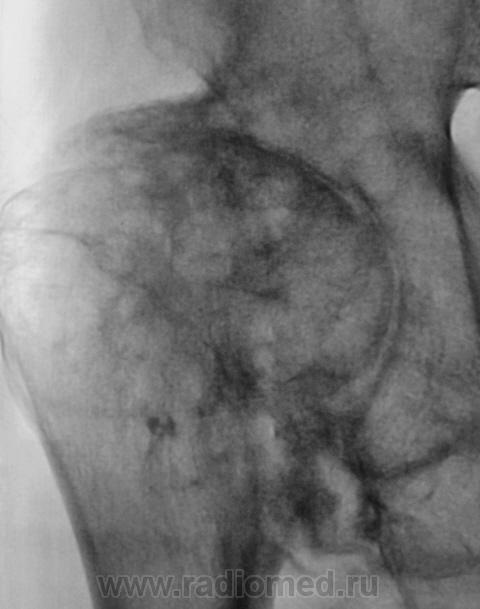

"Спинальный больной". Наблюдение Бородулина М.А. Наблюдение Бордулина М.А. Наблюдение Катенёва В.Л. Пт, 06/07/2012 - 21:41 #1 Наталия Васильевна Не на сайте Был на сайте: 5 лет 7 месяцев назад Зарегистрирован: 25.09.2011 - 09:02 Публикации: 754 А возможны ли такие изменения при сирингомиелии? Пт, 06/07/2012 - 22:22 #2 Катенёв Валенти... Не на сайте Был на сайте: 6 лет 11 месяцев назад Зарегистрирован: 22.03.2008 - 22:15 Публикации: 54876 По всей видимости - да. Пт, 06/07/2012 - 23:03 #3 И.Бондаренко Не на сайте Был на сайте: 1 день 9 часов назад Зарегистрирован: 13.09.2011 - 22:55 Публикации: 9199 Считайте ,что такие изменения сопутствуют сирингомиелии. Пт, 06/07/2012 - 23:08 #4 Катенёв Валенти... Не на сайте Был на сайте: 6 лет 11 месяцев назад Зарегистрирован: 22.03.2008 - 22:15 Публикации: 54876 И.Бондаренко wrote: Считайте ,что такие изменения сопутствуют сирингомиелии. +1 Сб, 07/07/2012 - 22:10 #5 Наталия Васильевна Не на сайте Был на сайте: 5 лет 7 месяцев назад Зарегистрирован: 25.09.2011 - 09:02 Публикации: 754 Ну, тогда, действительно-"спинальный больной".

А возможны ли такие изменения при сирингомиелии?

По всей видимости - да.

Считайте ,что такие изменения сопутствуют сирингомиелии.

Ну, тогда, действительно-"спинальный больной".